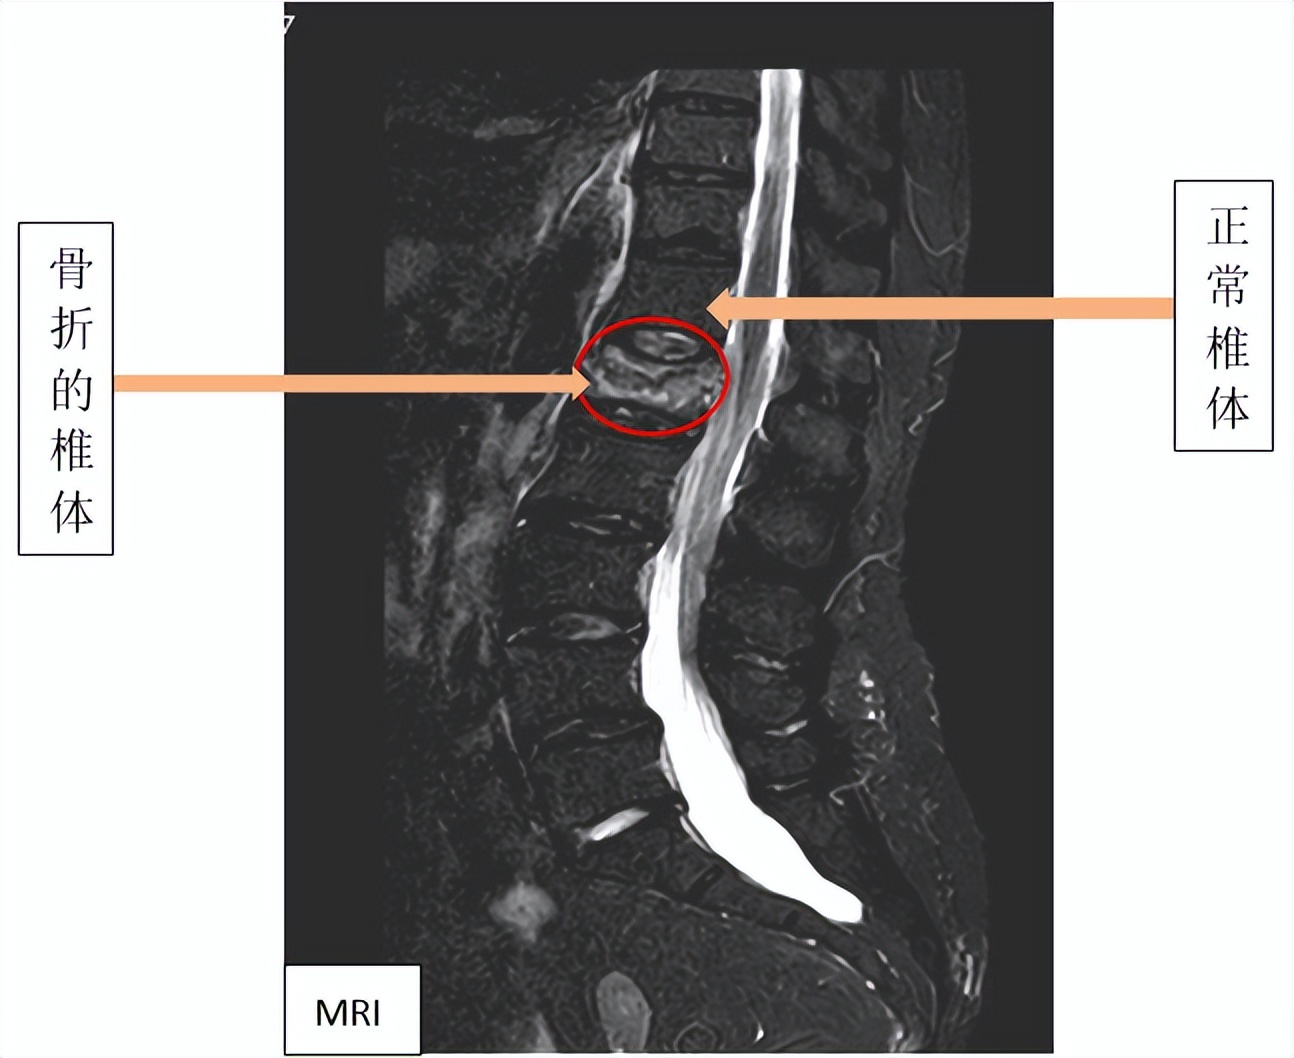

影像学检查

常用的有X线、CT、MRI、骨扫描。